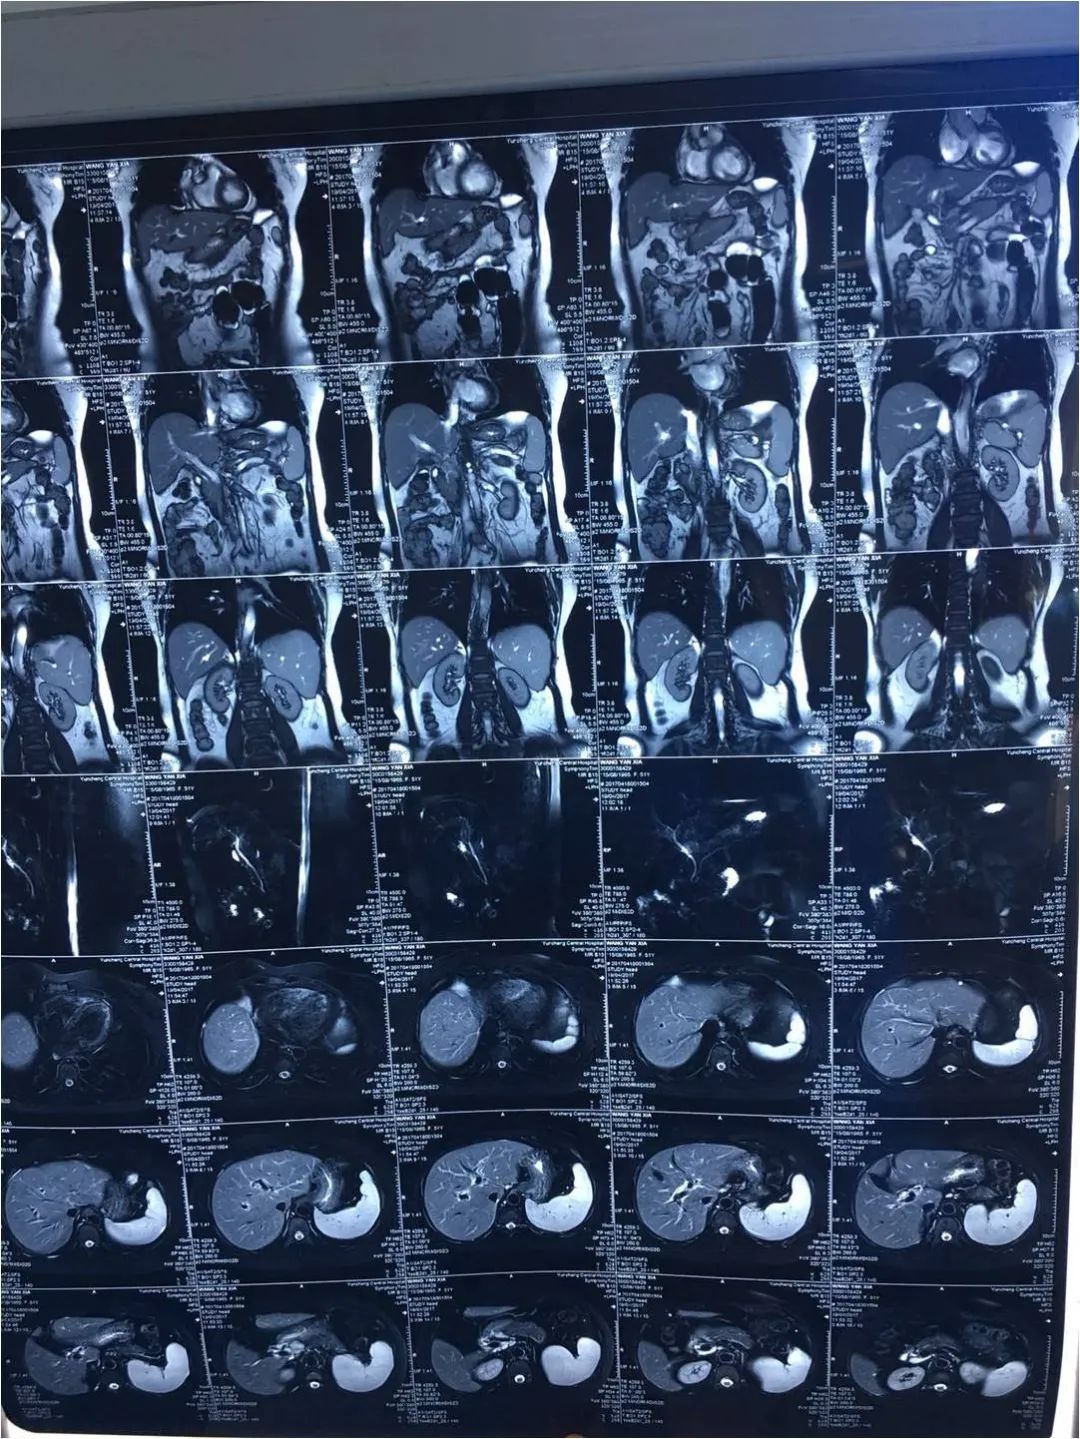

和患者沟通行MRCP检查大胆管,排除硬化性胆管炎,MRCP检查结果如下:

原发性硬化性胆管炎;脂肪肝;胆囊摘除术后;子宫卵巢切除术后。

PSC发病隐匿,好发于男性,发病机制涉及自身免疫反应,与遗传易感性、肠道淋巴细胞归巢假说、肠漏假说、胆汁酸-微生物相互作用等因素有关; 以慢性胆汁淤积(GGT、ALP升高)、胆管弥漫性炎性浸润、纤维化、阶段性狭窄为主要特征 ;可检测出多种自身抗体:ANA、pANCA、SMA、抗磷脂抗体、抗内皮细胞抗体等,但均缺乏特异性; 影像学特征为肝内外胆管呈枯树枝样改变 ;常合并溃疡性结肠炎。

该患者肝活检病理检查提示PSC,建议查大胆管,但MRCP不支持 ,是否与穿刺前已经使用激素、免疫*制剂抑**有关?或者此患者为小胆管型PSC重叠AIH?结合PSC可合并炎症性肠病的疾病特点,可考虑行肠镜检查。另外,有合并IgG4相关性胆管炎的可能,可行IgG4检查。病理考虑PSC后可加用足量牛磺熊去氧胆酸治疗;病理考虑脂肪肝,可加用多烯磷脂酰胆碱等治疗,观察疗效。